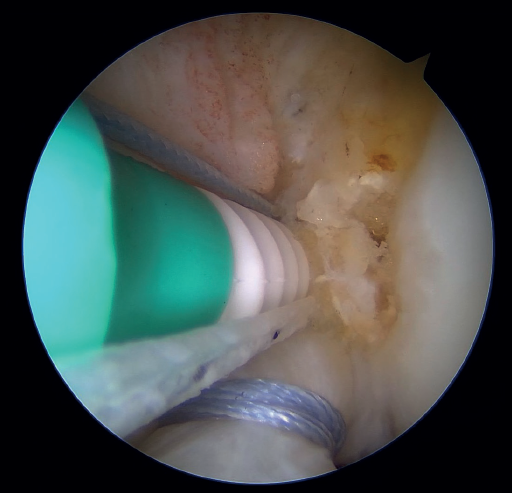

Once a good view of the central compartment is obtained, the area of the femoral footprint of the ACL is prepared to leave exposed bone, and microperforations are made in the medial wall of the lateral condyle to leave a bleeding bed to favor healing of the ligament (Figure 3). These microperforations can be made using specific instruments or with the implant punch. The advantage of using the punch is that the implant insertion site can be prepared at the same time, and only one instrument is used for the entire process (Figure 4). This step can be done after the suture has been prepared in the ligament, although doing it beforehand avoids the threads from standing in the way. The ideal point for fixation is just anterior to the native ACL footprint, although if the tear is partial or corresponds to Sherman I, it can be taken to the anatomical footprint without difficulty.